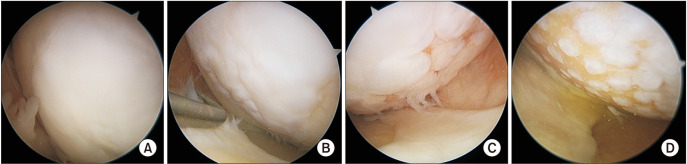

Methods: Patients who underwent medial open-wedge HTO from 2010 to 2022 with a minimum 2-year follow-up were retrospectively reviewed. Patients were divided into 2 groups: HTO + combined cartilage procedures (C group) and isolated HTO (I group). C group was further divided into 2 subgroups based on the medial femoral condyle (MFC) cartilage status assessed on second-look arthroscopy: well-regenerated cartilage (C1 group) and poorly regenerated cartilage (C2 group). Propensity score-matched I groups were formed for each C1 and C2 group (C1-matched and C2-matched group I), based on baseline factors affecting clinical outcomes. Comparative analysis was performed for each matched pair based on patient-reported outcomes (PROs).

Results: A total of 313 patients were retrospectively reviewed in this study, with 199 patients included in the analysis: 83 patients in the C group (49 in the C1 group and 34 in the C2 group) and 116 patients in the I group. Baseline characteristics showed no significant difference between the matched groups after propensity score matching. The mean follow-up period for all groups was approximately 3 years with no significant differences. The C1 group showed significantly better PROs and improved PROs at the final follow-up compared to the C1-matched I group (visual analog scale score, p < 0.001; Lysholm, p = 0.004; Knee injury and Osteoarthritis Outcome Score subscales, p ≤ 0.018). However, the C2 group did not show any differences in PROs compared to the C2-matched I group at the final follow-up.